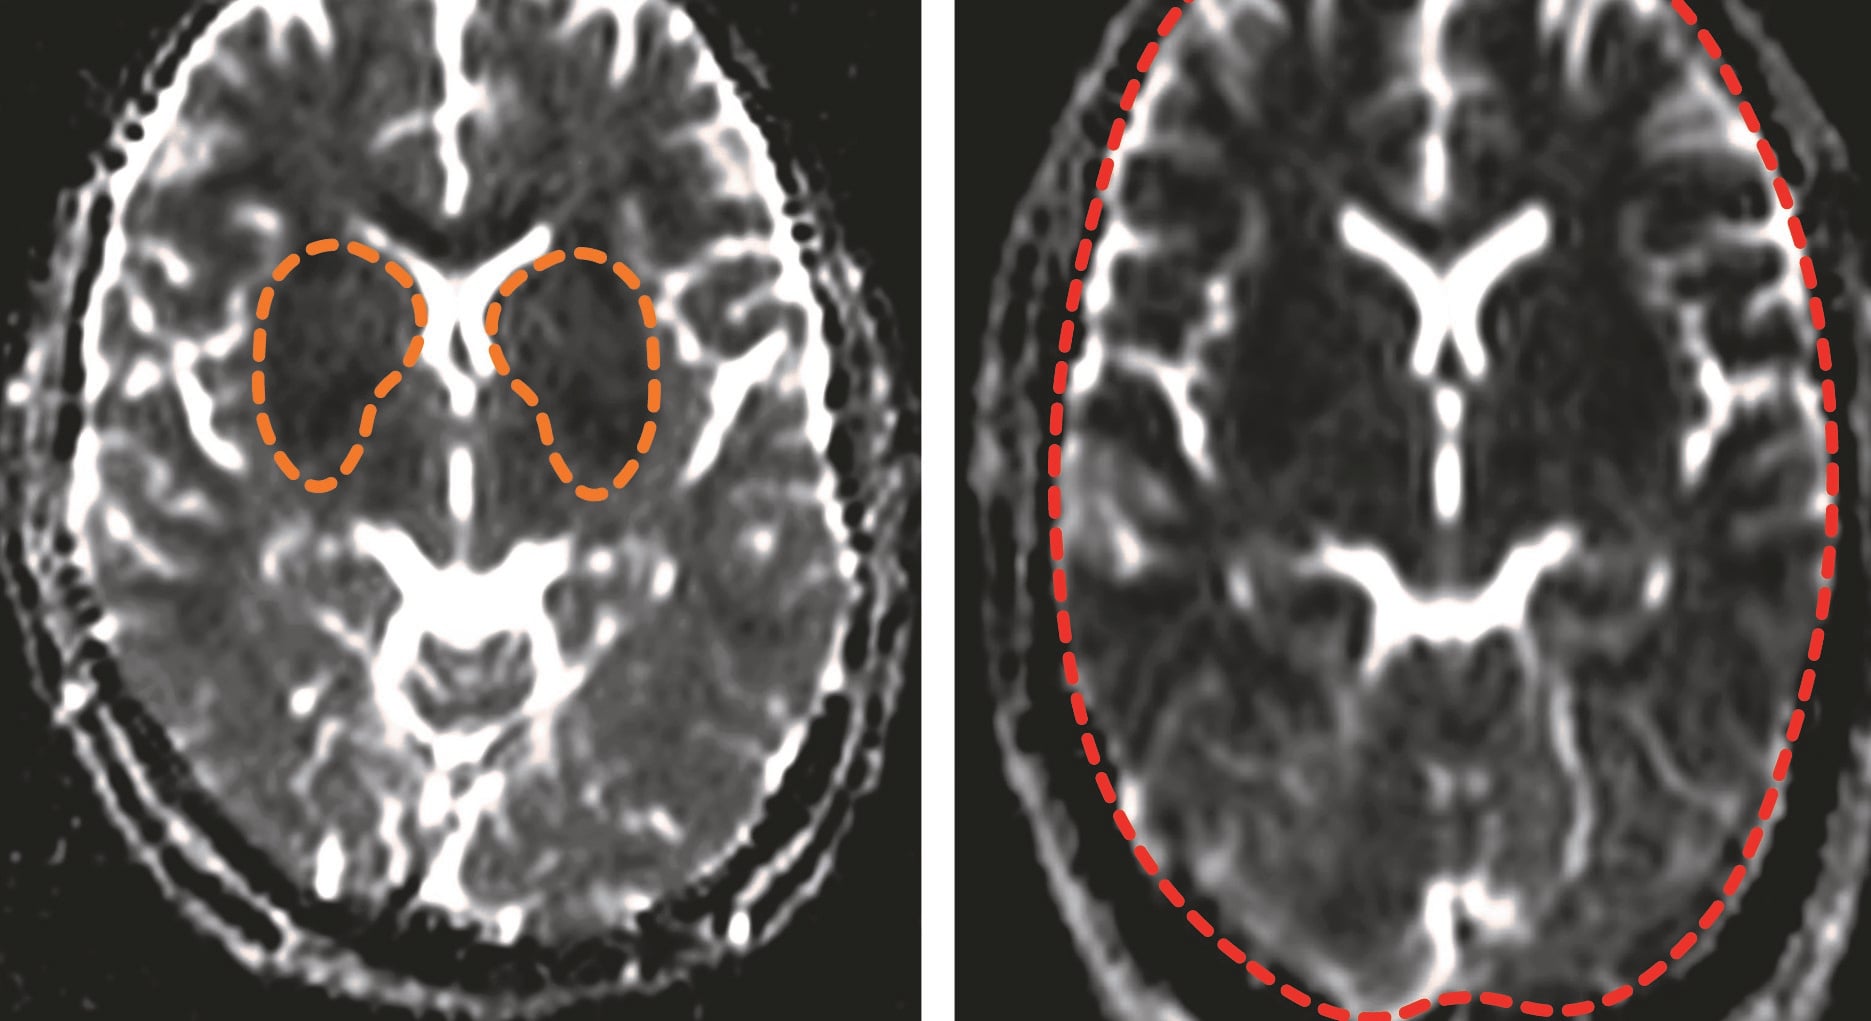

From www.ajnr.org

DiffusionWeighted MR Imaging in a Prospective Cohort of Children with Cerebral Malaria Offers Medicine For Brain Malaria It’s essential to seek treatment right away if you think you have malaria or have visited an area where it is common. Treatment of severe and cerebral malaria. All patients with plasmodium falciparum malaria with neurologic. Treatment is with parenteral artemisinin derivatives and electrolyte correction, usually in the setting of an intensive care unit, as well as symptomatic treatment (e.g.. Medicine For Brain Malaria.

Imaging Cerebral Malaria with a SusceptibilityWeighted MR Sequence American Journal of Medicine For Brain Malaria All patients with plasmodium falciparum malaria with neurologic. The right medication and correct dose can treat malaria. It’s essential to seek treatment right away if you think you have malaria or have visited an area where it is common. Ensure prompt diagnosis followed by immediate treatment. Treatment of severe and cerebral malaria. Treatment is much more effective when it’s started. Medicine For Brain Malaria.